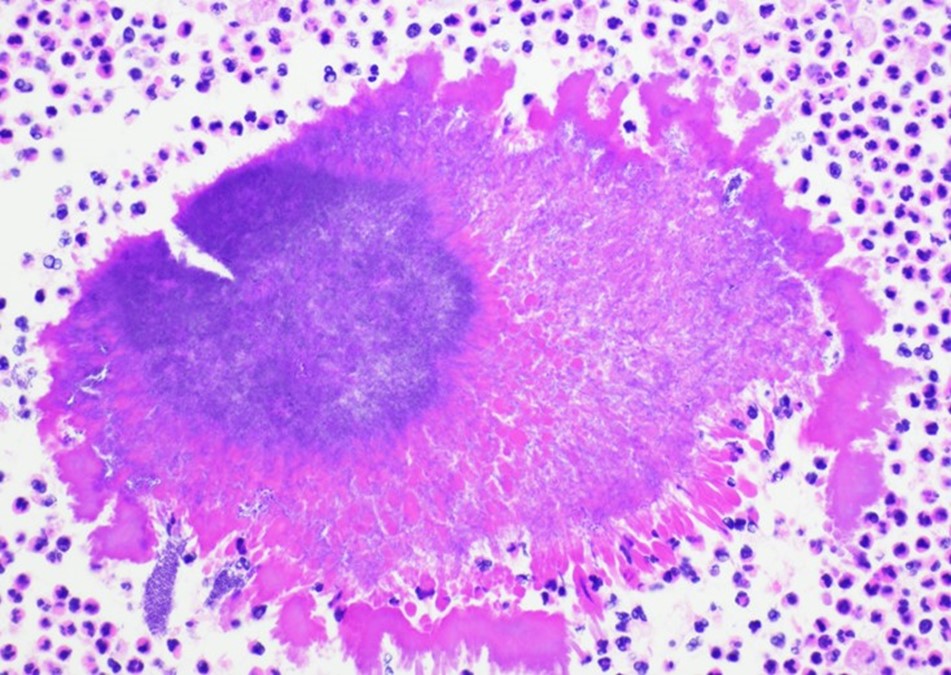

On admission, a CT scan of the abdomen and pelvis revealed a 3.5 x 1.9 cm air and fluid collection of the inferior border of the spleen and 5.2 x 1.6 cm fluid collection of lateral spleen. The collections were noted to be increased compared to the prior imaging 6 weeks before. Blood cultures were without growth at 5 days. A transthoracic echocardiogram showed no significant valvular abnormalities or vegetations. On hospital day 5, the patient was taken to the operating room for a laparoscopic splenectomy and left diaphragm repair. Surgical findings included a large spleen with omental adhesions and a thick rind along the spleen, which was closely adherent to the diaphragm. A portion of the colon closely adherent to the spleen was also noted. Histopathologic examination showed multifocal splenic abscesses with surrounding fibrosis on hematoxylin and eosin (H&E) stain and granules with surrounding Splendore-Hoeppli material on higher magnification (Figure 1). On Grocott-Gomori methenamine silver (GMS) stain, the granule was seen to be composed of mixed bacterial morphologies with a predominance of filamentous rods typical of Actinomyces (Figure 2). Based on histopathological examination, a diagnosis of splenic actinomycosis was rendered.

Although most actinomycotic lesions are polymicrobial, species of the genus Actinomyces are the predominant etiologic agents.2 Actinomyces are a group of gram positive filamentous facultatively anaerobic or microaerophilic bacteria that are normal flora of the gastrointestinal and genitourinary tracts. The organisms typically have true branching and may appear beaded due to irregular Gram staining. Importantly, Actinomyces spp. will be negative with modified acid-fast staining, which can be used to differentiate it from Nocardia spp. The bacteria are relatively slow growing on primary culture and mature colonies may have a variety of morphologies. The classic “molar tooth” appearance is characteristic of A. israelii.3 On histopathology, actinomycotic lesions have a surrounding area of fibrosis and central suppurative inflammation with granules. The granules consist of accumulations of organisms with club-shaped ends and filamentous rods seen on special staining.4 Optimal diagnosis would consist of visualization of these features on histopathology or other direct method. Isolation of the organism can be useful but should be taken in the context of the clinical picture as the mere isolation of Actinomyces in culture does not always imply actinomycosis.